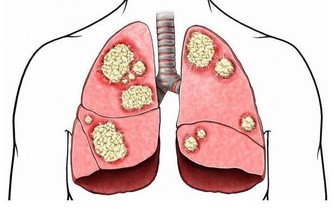

當慢性淺表性胃炎發展為慢性萎縮性胃炎時,胃黏膜常伴有腸上皮化生,也就是說胃里長出了本該在腸道才有的細胞,而且正常胃黏膜的分泌功能改變為腸道的吸收功能。由於胃黏膜對吸收的東西無法解毒,天長日久,在部分患者胃內局部形成致癌物質,因此“腸上皮化生”又被稱為癌前病變。

近年來

“腸上皮化生”的患者越來越多,已佔胃腸病患者的一兩成,而且有年輕化趨勢,尤其是在精神壓力較大的都市白領人群中更明顯,這和飲食不規律、壓力大等都可能有關。

臨床統計結果表明,部分“腸上皮化生”會發展為胃癌,但正常人的胃裡也會有“腸上皮化生”,因此不必過分緊張,但應引起足夠重視。

2.腸化生:有小腸型與大腸型兩種,小腸型(完全型)具有小腸黏膜的特徵,分化較好。大腸型(不完全型)與大腸黏膜相似,又可分為2個亞型:Ⅱa型,能分泌非硫酸化黏蛋白;Ⅱb型能分泌硫酸化黏蛋白,此型與胃癌發生關係密切。